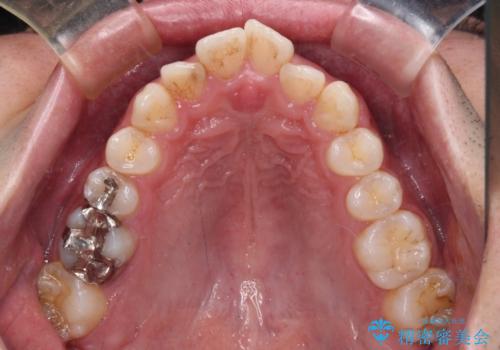

- 上下前歯のデコボコと突出感を気にして来院された患者様です。

矯正治療後に銀歯をセラミックに替えたいとの要望があり、概ね歯列が整ったところで銀歯をセラミックに替え、仕上げにインビザライン1セットを使用して最終的に歯列を整えました。